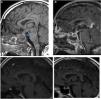

MRI revealed a cystic collection in the hypothalamus with restricted diffusion of 12 × 9 × 11 mm connected to another image in the pituitary of 14 × 12 × 8 mm, findings consistent with hypothalamic-pituitary abscess (Fig. 1. A and B).

Pituitary MRI images.

A: Sagittal T1 without contrast revealing hypothalamic-pituitary occupation with infundibular (pituitary stalk) thickening, which with the introduction of contrast (B) reveals peripheral enhancement and cystic content. C: Follow-up MRI one month after diagnosis: disappearance of the hypothalamic abscess. Persistence of an infiltrative lesion in the pituitary gland and in the pituitary stalk. D: Follow-up MRI at 6 months. Resolution of the hypothalamic-pituitary abscess.

The patient continued follow-up in endocrinology; six months after the onset of the condition, the ACTH and ADH deficiency had recovered. The hypothalamic abscess had resolved in the first month MRI, and the pituitary abscess by the sixth month (Fig. 1C and D).

Typical features of the abscess on MRI include a totally or partially cystic mass in the sellar region, hypointense or isointense on T1, and hyperintense or isointense on T2, revealing peripheral ring enhancement after gadolinium injection (Fig. 1 B).5 In our case, it is notable that this pituitary lesion continues to the hypothalamus. However, this pituitary finding is not specific, since it is observed in Rathke's cleft cyst, in cystic craniopharyngiomas and in cystic adenomas; these characteristics are useful if there are compatible signs and symptoms. In pituitary apoplexy, bleeding on imaging evolves as follows: in the acute phase it is hypointense on T2, in the subacute phase it is hyperintense on T1 and hypo/hyperintense on T2, and in the chronic phase it is hypointense on T1 and T2.1,3,4,7